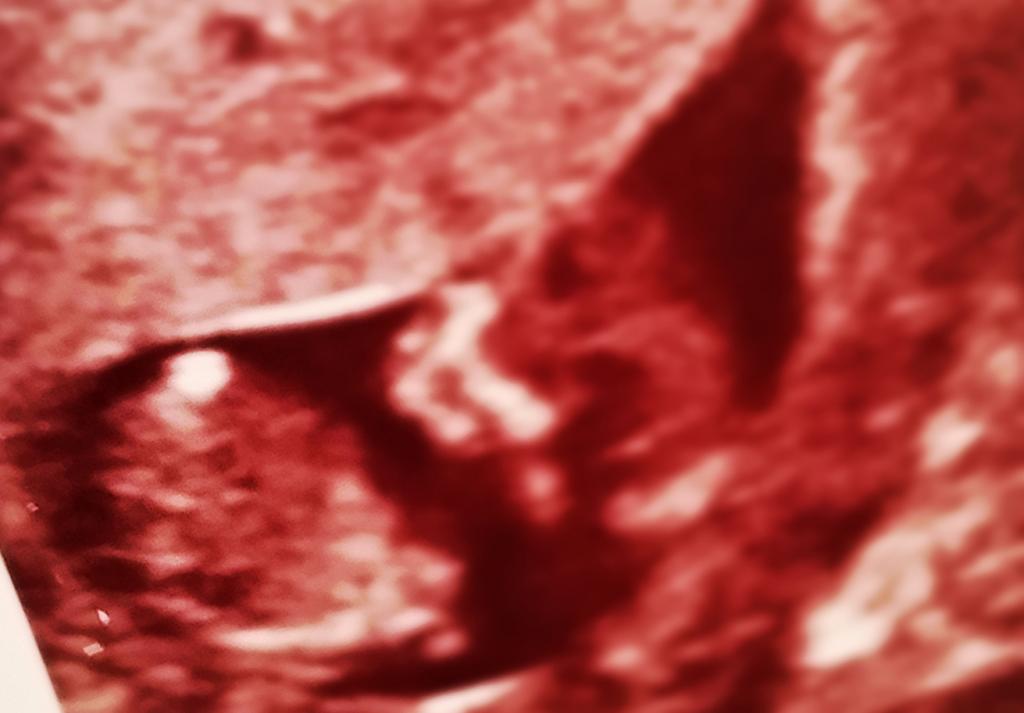

12 weeks 1 day

images are too small, but I don't think there is a nub in these shots

I wouldn't want to agree on that been the nub hun but if it is then defo pink x